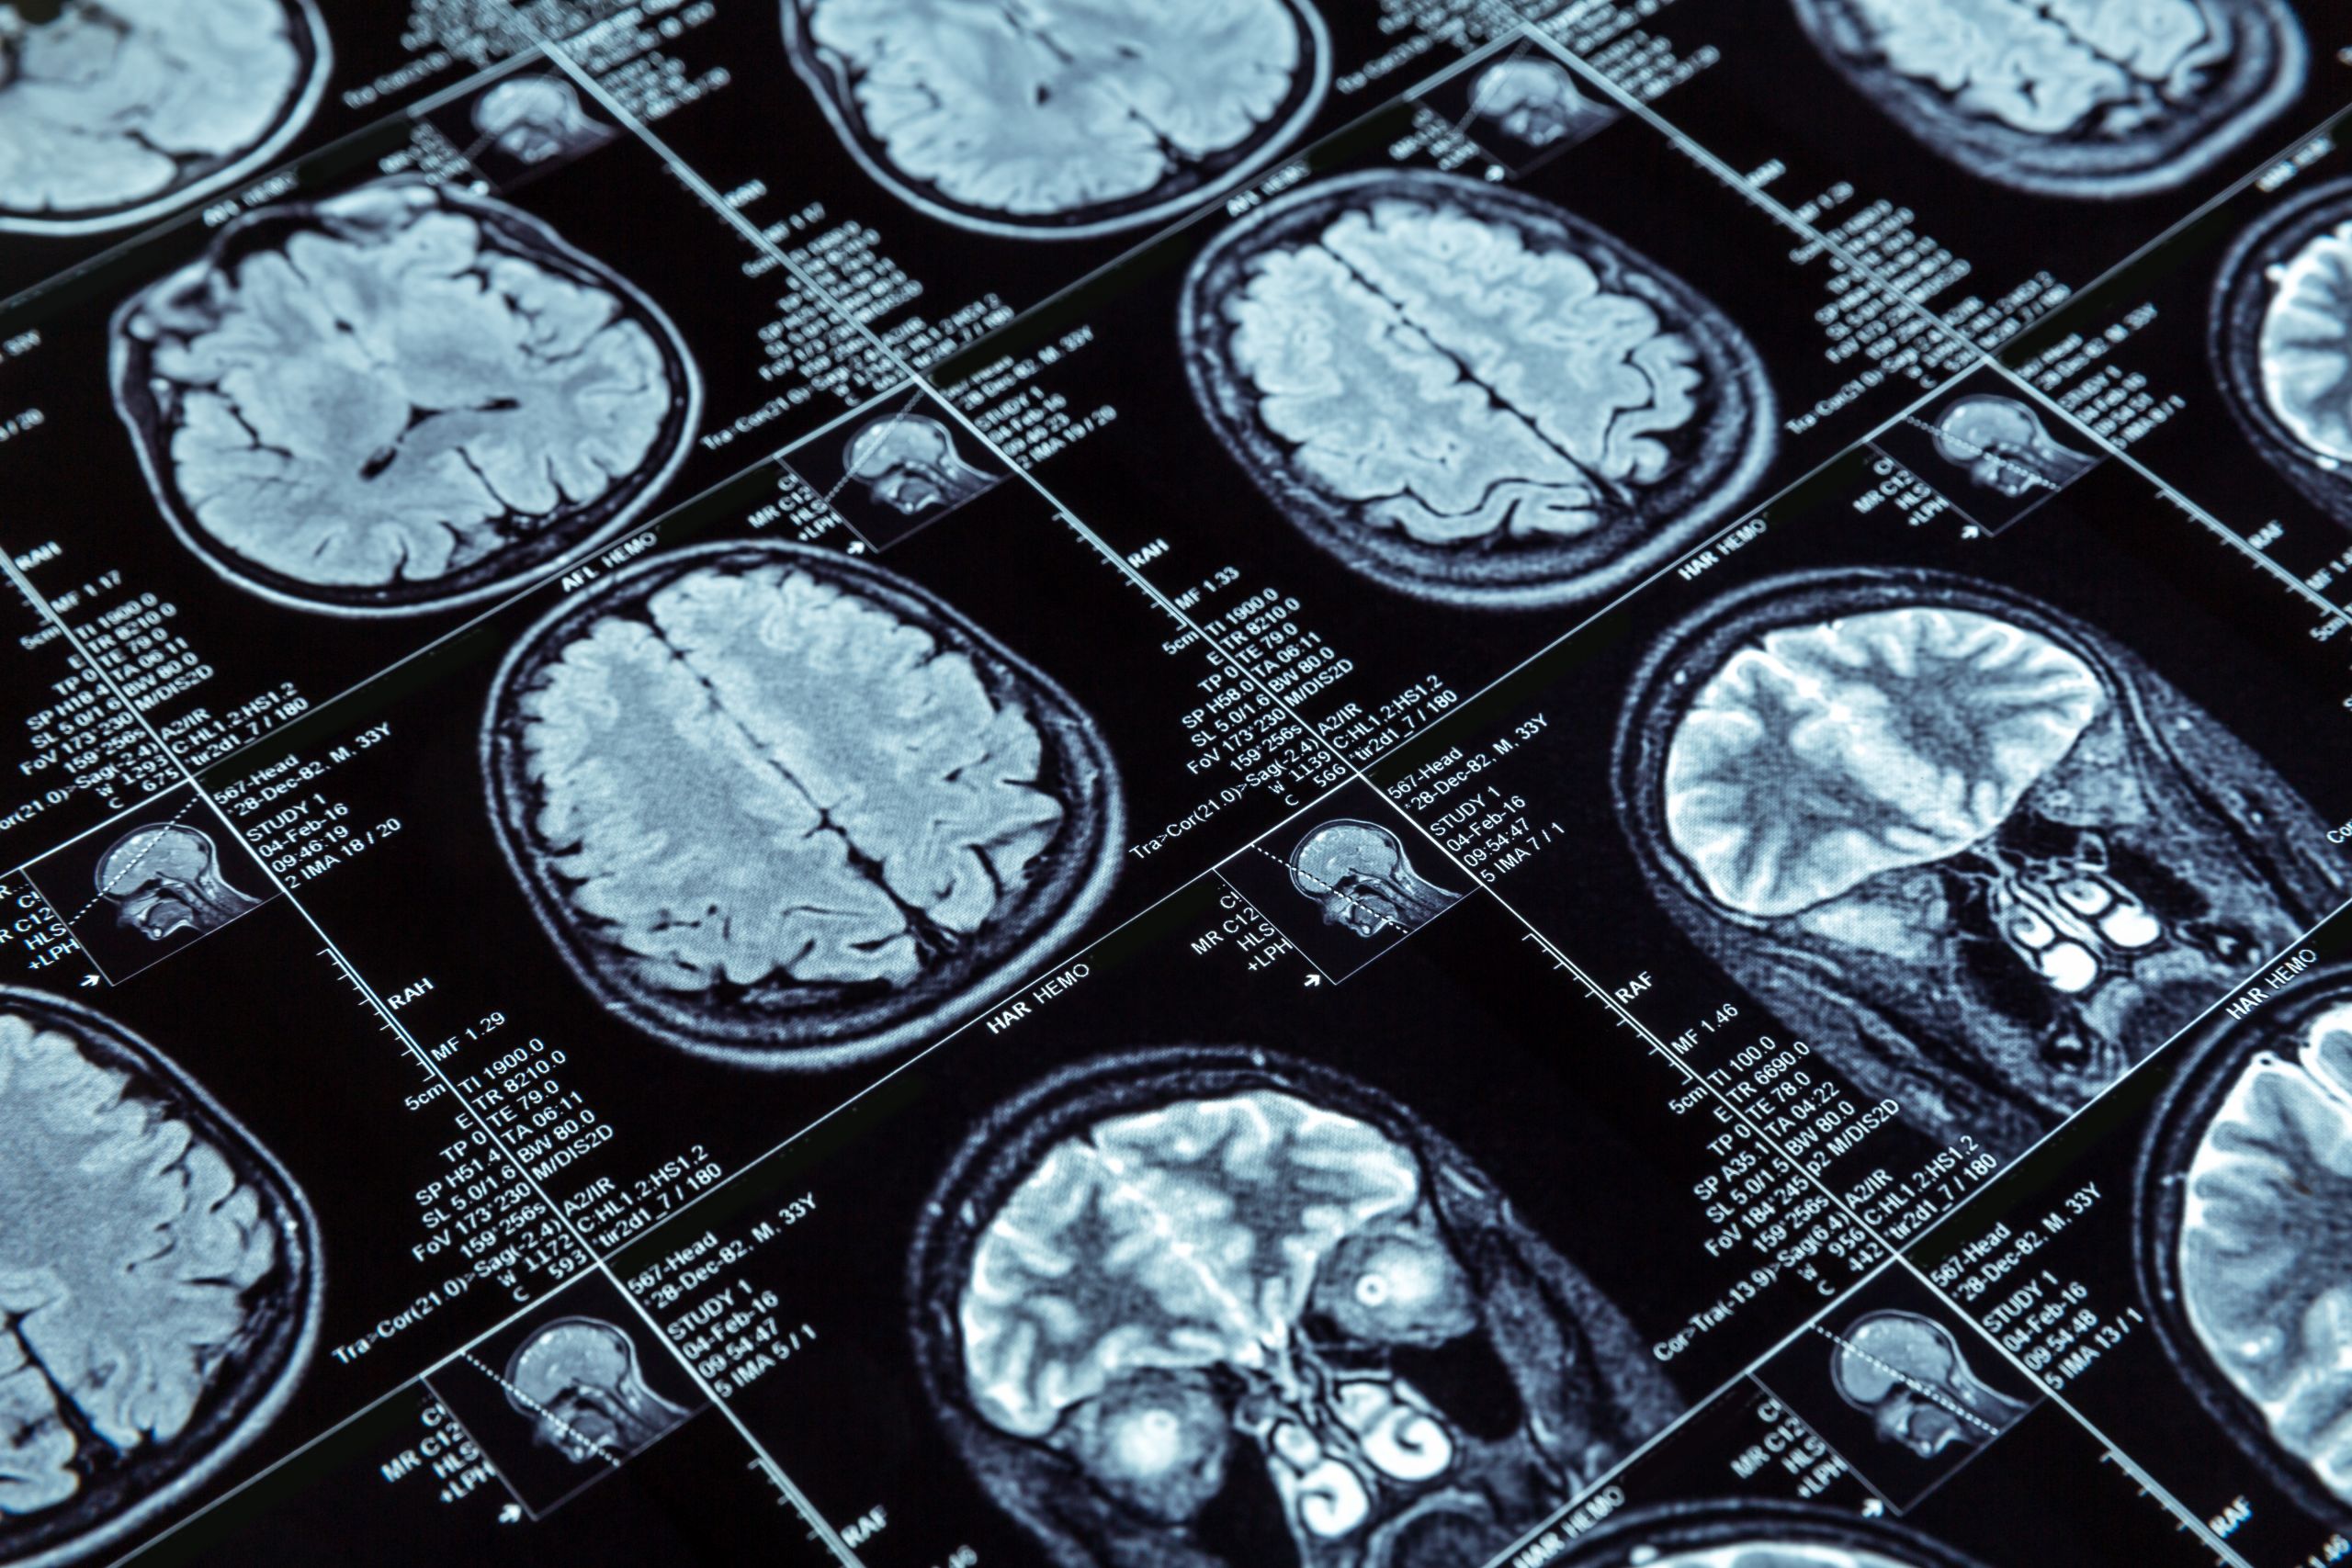

Ερευνητές στις ΗΠΑ, με επικεφαλής έναν Έλληνα επιστήμονα της διασποράς, αναπτύσσουν μια νέου τύπου θεραπεία για καρκίνους του εγκεφάλου, η οποία συνδυάζει νανοσωματίδια και εστιασμένους υπέρηχους, επιτρέποντας σε ισχυρά φάρμακα RNA να διαπεράσουν τον αιματοεγκεφαλικό φραγμό. Η θεραπεία δοκιμάστηκε με επιτυχία σε πειραματόζωα (τρωκτικά), ανοίγοντας το δρόμο για τη δοκιμή της σε ανθρώπους και αφήνοντας υποσχέσεις ότι μπορεί να αποτελέσει μελλοντικά μια νέα θεραπεία για τον καρκίνο του εγκεφάλου.

Το ριβονουκλεϊκό οξύ (RNA), το οποίο αποτελεί τη «ραχοκοκαλιά» των νέου τύπου εμβολίων που χρησιμοποιούνται κατά της νόσου Covid-19, θα μπορούσε, όπως δείχνει η νέα έρευνα, να χρησιμοποιηθεί και για τη θεραπεία εγκεφαλικών όγκων, οι οποίοι συχνά είναι ανθεκτικοί στη συνήθη χημειοθεραπεία και ακτινοθεραπεία. Οι ερευνητές διαπίστωσαν ότι ένας τύπος RNA, που ονομάζεται μικροπαρεμβαλλόμενος RNA ή siRNA, αν συσκευαστεί σε ειδικά νανοσωματίδια και συνδυαστεί με την τεχνική του «εστιασμένου υπέρηχου με μικροφυσαλίδες», μπορεί να διακόψει την έκφραση ορισμένων γονιδίων που οδηγούν σε καρκίνο.

Στη συνέχεια δοκίμασαν τη χρήση αυτής της μεθόδου με νανοσωματίδια σε ποντικούς, σε συνδυασμό με εστιασμένο υπέρηχο με μικροφυσαλίδες. Με την έγχυση ενός τύπου μικροσκοπικής αεριούχου φυσαλίδας, δέσμες υπερήχων χαμηλής έντασης που στοχεύουν στον αιματοεγκεφαλικό φραγμό του όγκου, προκαλούν στις φυσαλίδες δυνατές δονήσεις. Οι δονήσεις «διαταράσσουν» ένα μέρος του αιματοεγκεφαλικού φραγμού τόσο όσο χρειάζεται, ώστε να μπορούν να διεισδύσουν τα νανοσωματίδια που φέρουν το siRNA και να φτάσουν έτσι στα καρκινικά κύτταρα.

Σε ποντικούς με εγκεφαλικούς όγκους, η ερευνητική ομάδα μέτρησε με τη χρήση των υπερήχων δεκαπλάσια αύξηση στην ποσότητα τόσο των siRNA όσο και των νανοσωματιδίων που διαπέρασαν τον αιματοεγκεφαλικό φραγμό. Το siRNA που έφτασε στους όγκους, εξακολουθούσε να είναι ενεργό και διέκοψε την έκφραση ενός στοχοποιημένου γονίδιου. Αντίστοιχα, οι ερευνητές κατέγραψαν αύξηση στη θανάτωση του αριθμού των καρκινικών κυττάρων κατά 16 φορές περισσότερο, με τον συνδυασμό νανοσωματιδίων που φέρουν siRNA και υπερήχων, σε σύγκριση με τα νανοσωματίδια που φέρουν μόνο siRNA.